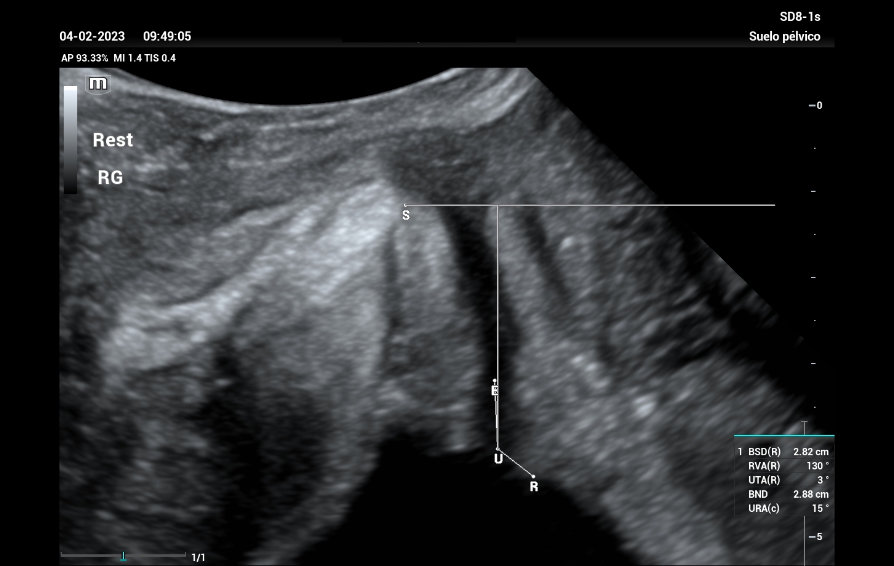

Bajo el tema ŌĆ£inspirando el cuidado de la salud de la mujerŌĆØ, se llev├│ a cabo en la Ciudad de Panam├Ī la primera conferencia de Nuewa Club en Latino America.?